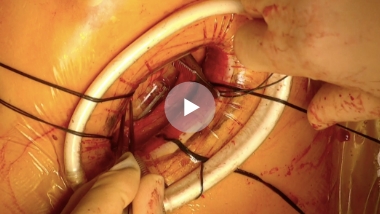

手術では悪くなった弁を切り取り、新しく人工弁を糸で縫い合わせていきます。手術は人工心肺装置を使い、心臓をいったん止めた上で行います。

僧帽弁は2つの弁と、心臓から弁を引っ張っている腱索というひも状の部分から成り立っています。手術では、切れた腱索の代わりに新しい人工腱索で補強したり、壊れた部分を切ったり縫い合わせたりして修復した後、弁の周りに特殊なリングを縫いつけて形を整えます。弁置換のようにワーファリンの内服は必要でなく、心臓の機能を温存でき長期成績も良好なため、弁形成術を第一選択としています。

当院では、僧帽弁形成術を行う場合には可能な限り全例に内視鏡手術で行っております。